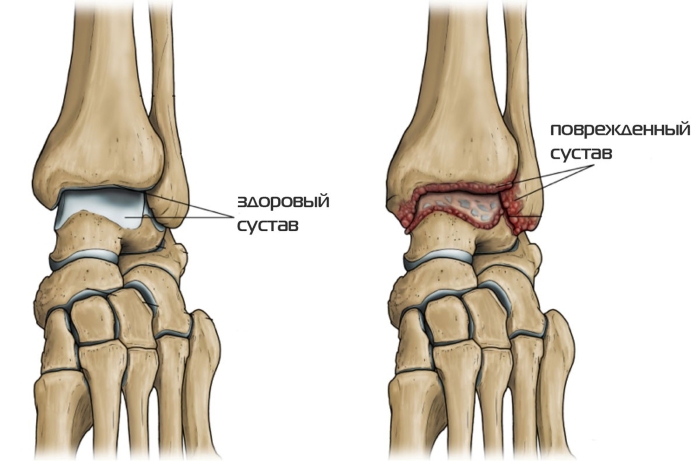

Артрит стопы, как и другие воспалительные процессы в суставах, сопровождается изменением состава синовиальной жидкости. Места соединения костей окружены специальной оболочкой, которая вырабатывает секрет. Эта жидкость предотвращает трение суставных поверхностей и доставляет полезные вещества в хрящевые ткани, а также удаляет токсины.

На начальных стадиях воспалительный процесс затрагивает только синовиальную оболочку, что называется синовитом. Воспаленные ткани начинают вырабатывать избыточное количество жидкости, которая накапливается в суставной полости, вызывая отечность. Синовиальный секрет при артрите не может выполнять свои функции, что приводит к постепенному разрушению хряща и костей.

- деформация сустава, видимая на изображениях;